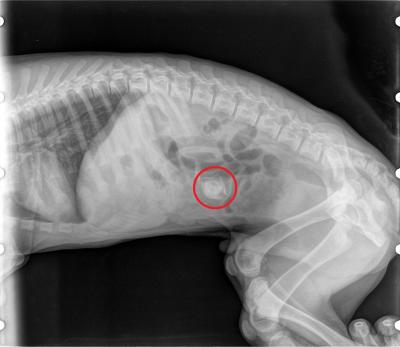

Pecka z broskve ve střevě způsobovala pejskovi bolesti břicha a úporné zvracení. Šipka ukazuje polohu cizího tělesa na RTG.

Naštěstí se podařilo pecku včas najít a odstranit.